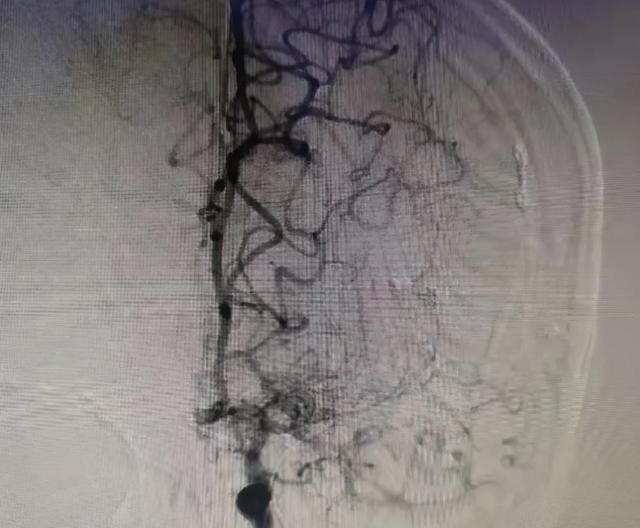

医生介绍,正常人颅内有六根动脉,分别为双侧前后中动脉,老人颅内缺少了双侧的中动脉,周边的毛细血管呈烟雾上升状从两侧代偿着主动脉功能,因此也称“烟雾病”,所谓的“少根筋”只是通俗的一种说法。

医生指着影像对采访人员说:“该病学名为脑底异常血管网症,张女士没有两侧的中动脉,这是先天就形成的生理结构,因中动脉缺失,两侧的毛细血管自下而上密布分枝,来代偿着中动脉的供血功能,在CT影像上就像升起的烟雾一样,因此该病又称烟雾病。”

医生介绍,烟雾病的病因仍不明确,临床女性多发,是以双侧颈内动脉末端及大脑前动脉、中动脉起始部狭窄或闭塞为特征,并继发颅底异常血管网形成的一种脑血管疾病。脑缺血和颅内出血是该病的两种主要危害,总体上以脑缺血为主。除了像张女士这样先天中动脉缺失的,还有后天因前、中动脉阻塞引起的。